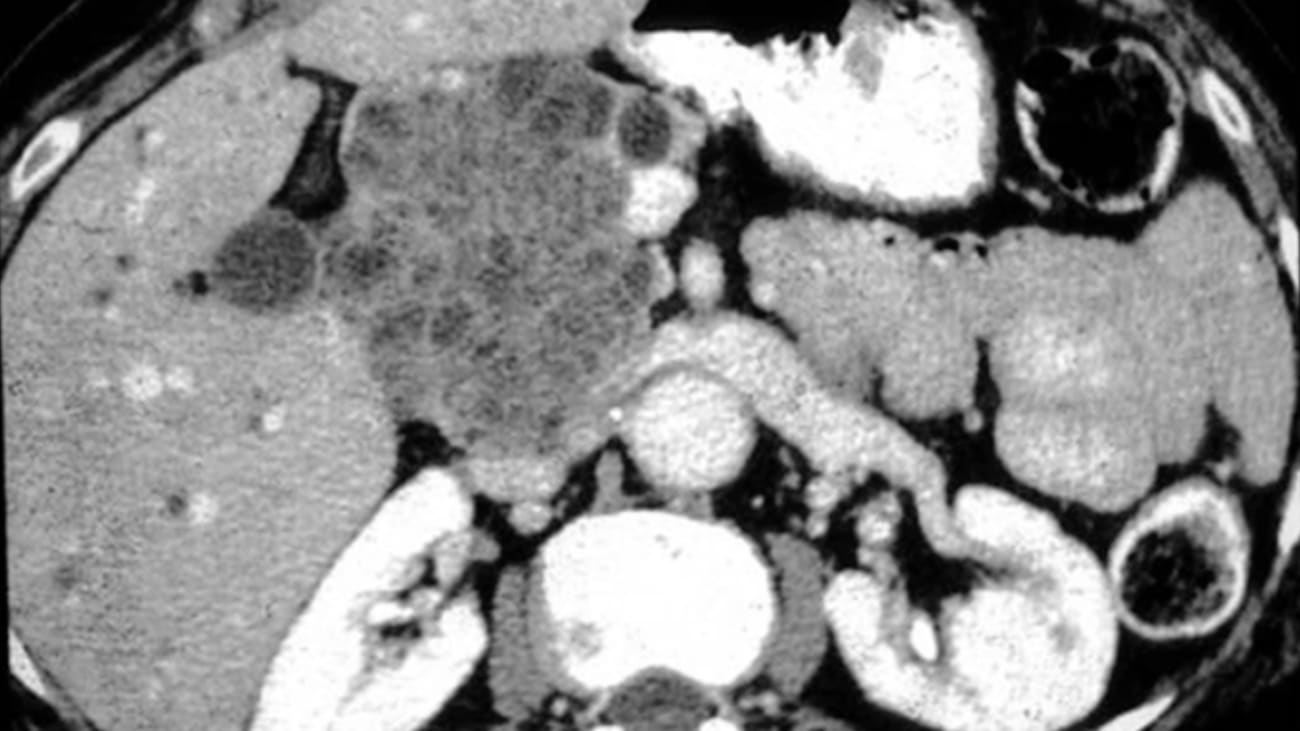

Hello thank you for joining us this afternoon. I would like to thank the course directors for inviting me to give this talk on pancreatic nia Pleasure. Today Our format will be questioned based so we'll start to go through the questions. A 68 year old woman presents to the emergency room with left lower quadrant abdominal pain. Ct scan reveals stool throughout the colon and also reveals a 2.5 centimeter assist in the pancreas mm. RCP confirms a multiple ocular 2.5 centimeter. Cyst in the pancreatic head which communicates with the branch of the main pancreatic duct. Her abdominal pain has resolved with a bowel regimen and she is otherwise asymptomatic. What is the next step in the management of the cyst? A surgical referral for pancreatic duodenal ectomy surveillance with us in 3 to 6 months. MRI or endoscopic ultrasound in 6 to 12 months or an MRI in 12 months. If you're perplexed, it's because we we have multiple guidelines that recommend multiple different options as acceptable and we'll go through some of the data behind them. So first what's all the fuss about? Well, pancreatic cysts can broadly be divided into those that are non neo plastic and we don't have to worry about them. Benign neo plastic with malignant potential or no malignant potential. Those with no malignant potential include are serious cyst adenomas and those with malignant potential include our introductory papillary music Disney. Applause ums or iP men's and the muse. Narcissistic nia possums or coons pancreatic cysts that are malignant include adenocarcinoma, neuroendocrine tumors solid suited popularity us and other lesions. How often do we see this? Well we see them a lot now with an aging population. More imaging is performed. And in this interesting study that was published in C. G. H. About almost a decade ago we looked at the incidence of cysts and the number of patients who had cysts by age. What you can see here is this prevalence clearly increases with age. Overall. About two and a 1/2% of all subjects had cysts in the pancreas with no differences in gender. One of the most common cysts that we see our branch chuck I. P. M. S. These are cysts that have no involvement of the main pancreatic duct. They're tipple are typically multi lobular, multi cystic and separated. An M. R. C. P. May show communication with the main pancreatic duct. 40% of patients may have multiple branch duct I. PMS and they can occur anywhere in the pancreas. They are often diagnosed in patients who are between 50 and 70 years old. You can have this characteristic appearance on M. R. C. P. What about concerning features? What should we worry about? Well there are features that have high risk of stigma of malignancy and these include obstructive jaundiced enhancing rural modules and a main pancreatic duct that's over 10 and then we have other features which are worrisome and concerning including pancreatitis Cyst size over three cm and enhancing mural nodule less than five millimeters. A main duct between five and nine millimeters, abrupt change in the caliber of the pancreatic duct with distal atrophy lymphedema apathy increased serum C A. 99 or cyst growth rate greater than five millimeters over the course of two years. Overall, the more worrisome features we haven't assist, the higher the risk of progression to. So what happens to these patients with cyst, I think traditionally were taught to just follow the cyst. But what's interesting is that because cysts are found more often in older individuals, older individuals sometimes carry significant comorbidities. So this study that was published in the American Journal of Gastroenterology actually characterized cysts as low risk or high risk um and high risk uh assists were those that had any of our concerning features that we reviewed on the previous slide, um or low risk patients, or high risk patients. And a high risk patient was one who had a charleston score which was greater than equal to three. And they looked at both pancreatic cancer mortality as well as non pancreatic cancer mortality. With a reference group being those who had low risk patients and low risk this for the group that had low risk patients. Um and a high risk cyst. The risk of pancreatic mortality was greater than the risk of non pancreatic mortality, but for those who had a high risk patient. And and also a low risk cysts. Um Non pancreatic cancer mortality was actually greater than the pancreatic cancer mortality. And for the high risk patient who also has a cyst which features high risk features um risk of pancreatic mortality is also quite high. Um But we can see elevations significant elevations in non pancreatic uh mortality as well. Mhm. So what to do? We have multiple guidelines that have been published by multiple groups throughout asia. The A. S. G. Has recommendations. The A. G. A. Weighed in. Um And then A C. G. Has also made recommendations recently. And the european groups also have this In 3-6 months and then everyone year alternating MRI with endoscopic ultrasound. With the consideration for surgery if the patient is young and fit. Yeah. Mhm. The A. G. A. guidelines for management of a symptomatic pancreatic cysts recommend that we look at the cysts on imaging and evaluate whether or not there are two or more positive features which include a dilated main pancreatic duct assist that is greater than three cm or a solid component. Our patient uh If yes um then we proceed to us or F. N. A. R. Patient did not have this and so we repeat the MRI one year then by and only two to your five if any positive features develop at any point during surveillance. We move over to endoscopic culture sound. Um And if not it's important to note that the A. G. A. Guidelines suggest it's possible to stop surveillance after five years if there's any interval change and positive features at any point during five year surveillance we can move to repeat endoscopic ultrasound and F. N. A. Most pancreatic experts however, based their clinical decisions based on the Fukuoka guidelines where we reviewed on. Right So what about the question of stopping surveillance? Uh this is a study published in gastroenterology in 2017. Um looked at a variety of cysts uh in patients with maximum cyst size up to nine cm and looked at the duration of follow up and when malignancy developed. And we can see here at the five year interval Um that we have multiple cysts turning into cancer before that. But we also have uh several red dots to the right of this interval. Um and actually the risk of malignancy within three years was 4.3%. Uh And the risk of malignancy after five years. Almost 5.5% suggesting that uh we should continue surveillance despite some of the A. D. A. Record. Yes sir. So moving on Question two. We repeat the MRI in one year and it shows us now that the cyst has grown to three centimeters with suggestion of a mural nodule endoscopic ultrasound confirms the presence of an eight millimeter mural nodule and F. N. A. Was performed cyst fluid C. E. A. Was 2800 cytology was billed scant cellular charity and was diagnostic. What is the next best step in management for her now A repeat MRI in six months. Be checked peripheral blood ceo and recommend resection if greater than 192 repeat endoscopic ultrasound in one year D. E. R. C. P. Or E. Discussing multidisciplinary tumor board and consider resection. The correct answer is E. And if we follow through the Fukuoka guidelines at this point, our patient does now demonstrate one of the worrisome features being the nodule. And if we evaluate that we perform an endoscopic ultrasound which confirms the nodule and then we move on to consider surgery. Well what about main duct I. P. M. Ends these R. I. P. M. Ends with primary involvement of the main pancreatic duct which results in diffuse main pancreatic duct dilation. This can be seen on imaging on the top with a C. T. Scan with a very dilated pancreatic duct. We can also see it on this M. R. C. P. On the bottom left. Um And here we can see an endoscopic view with um Houston extruding from the papillon. Yeah in this case we need to exclude obstructive malignancy is a cause for pancreatic duct dilation. These lesions have a high risk of malignancy And reception is recommended for those that have a pancreatic duct greater than 10 in diameter. The pancreatic duct between five and 9 mm is considered worrisome and close observation is warrant. Question three. A 38 year old woman presents the emergency room with diarrhea and abdominal pain after eating at a fast food taco joint. She undergoes a CT scan which reveals colitis in the left colon and stool PcR demonstrates salmonella. Incidentally a 2.8 cm updated cystic lesions identified in the pancreatic tail with peripheral calcifications. Yeah. A typical image can be seen here on the right with assists and the peripheral calcifications. Mhm. Which of the following is true of this lesion. one. She should be referred for surgical reception to the cyst has ovarian likes troma three. Cyst fluid. CIA is less than five for it occurs with equal frequency in men and women. five It's a benign lesion and no further follow up is needed. Yeah. Yeah. Actually took There's one and 2. So this is amusing narcissistic. Nia plasm essentially exclusively occurs in women. Typically middle aged ovarian stromal seen on pathology is basically a diagnostic hallmark. Usually occurs in the tail of the pancreas but can be seen in the body. Typically imaging demonstrates substations and peripheral calcifications and it does have malignant potential similar to I. P. M. N. Given the young age of patients the location in the distal pancreas which allows for a distal pancreatic to me. Unknown malignant potential surgical section is almost always indicated in suitable surgical candidate. Yeah. Another type assist is a serious cyst adenoma which mostly occurs in women between the ages of 80 and 85. There are characteristic large micro cystic lesions compared comprised of a numeral very tiny cystic spaces giving a honey comb to parents. It can appear like a solid lesion on a CT scan an M. R. C. P. And or endoscopic ultrasound is often diagnostic based on appearance. This classically essential calcification which can be readily visible on C. T. And this lesion has no malignant potential and receptions only indicated if it's causing symptoms related to size. Cyst fluid C. E. A. Is often less than five nanograms from millimeter. Yeah so what is the deal with cyst fluid C. A. Cyst fluid ce a greater than 1 92 nanograms per milliliter suggests amusement assist. The music assists are the assist that typically have neo plastic potential and malignant potential. However it's only 80% sensitive which means you miss 20% of cysts and 80% specific, which means there's 20% false positive and this is fluid see A. Level does not predict malignancy. The higher the CIA the more specific so assist fluid CIA over 1000 is almost definitely amusement assist with about 99% specificity but it's an assist fluid. See a less than five is almost definitely not um use genesis but everything in the middle can be somewhat of a grey zone. A. C. E. A. Of 25 is still 50% likely amusement assist. Moving on to question # four A 63 year old woman with obesity and tobacco use asked about her risk for development of pancreatic cancer. Her medical history includes breast cancer at 52. Her father died of pancreatic cancer at 65 and her brother was just diagnosed three months ago with pancreatic cancer at 60. She comes to you to ask about her risks of developing cancer. Which of the following statements are true. Hey should be, she should be counseled to avoid tobacco smoke, be her risk of pancreatic cancer is 4.5 times that of the general population. See she should be tested for BRC one and BRC two mutations. And if that's negative, her risk of pancreatic cancer is the same as the general population. Or d no guidelines exist for screening this patient for pancreatic cancer. The correct answer is always to avoid tobacco smoke. Yeah. These are data that come from the Hopkins group that are now over 15 years old. Looking at the incidents of pancreatic cancer by the number of affected first degree relatives. First degree relatives are mother, father, sister, brother or Children. What they did was they compared the standardized incidence ratio so the rates of pancreatic cancer in the population with those who have affected first degree relatives To the incidents in the general US population, which at that time was nine for 100,000. What they found was that having one first degree relatives such as one parent Gives you a standardized incidence ratio of about 4.5. But this confidence interval crosses one and so having one first degree relative with pancreatic cancer does not significantly increased risk of pancreatic cancer in in the individual you're evaluating however, when there are two or more first degree relatives, as with our patient who has a parent and a sibling, The standardized instance ratio is approximately 6.4 and this is statistically significant and risk increases with increasing number of affected relatives in the family. Overall it does seem that 10 to 15% of patients who have pancreatic cancer do have familial aggregation or an inherited predisposition. And in fact the N. C. C. N. Updated its guidance this year to recommend germline hereditary genetic testing for all individuals with the diagnosis of pancreatic cancer and if that person is not available perhaps because they've passed away earlier and you're seeing a patient in the office, their first degree relatives. So usually their Children are also candidates for genetic testing. It should be known that smoking is the major known risk factor for this cancer. It's associated with about a third of all cases and it results rated tumor progression. And indeed when we're looking at incidents ratios for pancreatic cancer by smoking status for those in the Hopkins group who had at least one first degree relative with pancreatic cancer, you can see that the standardized incidence ratio for smokers, it was approximately three times that of the non smokers. Despite having similar family histories of pancreatic cancer, there are multiple other inherited syndromes that predisposed to pancreatic cancer. Um The hereditary breast and ovarian cancer as uh syndrome caused largely by mutations in B. R. C. A. One and B. R. C. A. Two carries an increased risk of pancreatic cancer. Drumline mutations in power bi to partner and localizer of B. R. C. A. Two is associated with breast cancer and pancreatic cancer. As our germline mutations in the ATM gene, familial atypical multiple mole melanoma or fam syndrome caused by mutations in C. D. K. And to a gives a much increased risk of pancreatic cancer. These individuals are also at risk for multiple nev. I just plastic nearby and melanomas patients with STK 11 mutations or put Diego syndrome are at incredibly high risk of pancreatic cancer, as well as hammer terminus polyps throughout the intestine breast colon, small intestine ovarian tumors, patients with lynch syndrome also have a modest increased risk of pancreatic cancer as well as the colon cancer, endometrial cancer and a variety of other tumors in patients who have hereditary pancreatitis are also at much increased risk of pancreatic cancer. Um And those with familiar Peloponnesus are also described to have an increased risk of pancreatic cancer, although this is modest are there risk factors do include chronic pancreatitis uh increased red meat processed meat obesity diabetes, which is a complicated story with diabetes being both a risk factor for um and possibly a consequence of the diagnosis of pancreatic cancer. Um and heavy out. Mhm. So who should be screened for pancreatic cancer. You should note that these consensus based guidelines were updated in gut last fall. Um But essentially those who have multiple meaning two or three affected blood relatives with at least one affected first degree relative. Um should be candidates for screening for pancreatic cancer. All patients with put Z. Eggers regardless of family history. And then the germline mutation carers for B. R. C. A. Two pal B to A. T. M. And lynch should undergo screening with one affected relative. B. R. C. A. Two mutation carriers can also consider screening when there are two affected family members. But no first degree relatives affected with pancreatic cancer screening typically occurs using MRI and or endoscopic culture sound with intervals of approximately one year and typically should be performed in large academic centers and under research conditions. Mm. With that, I thank you for your attention and we'll move on to the next speaker.